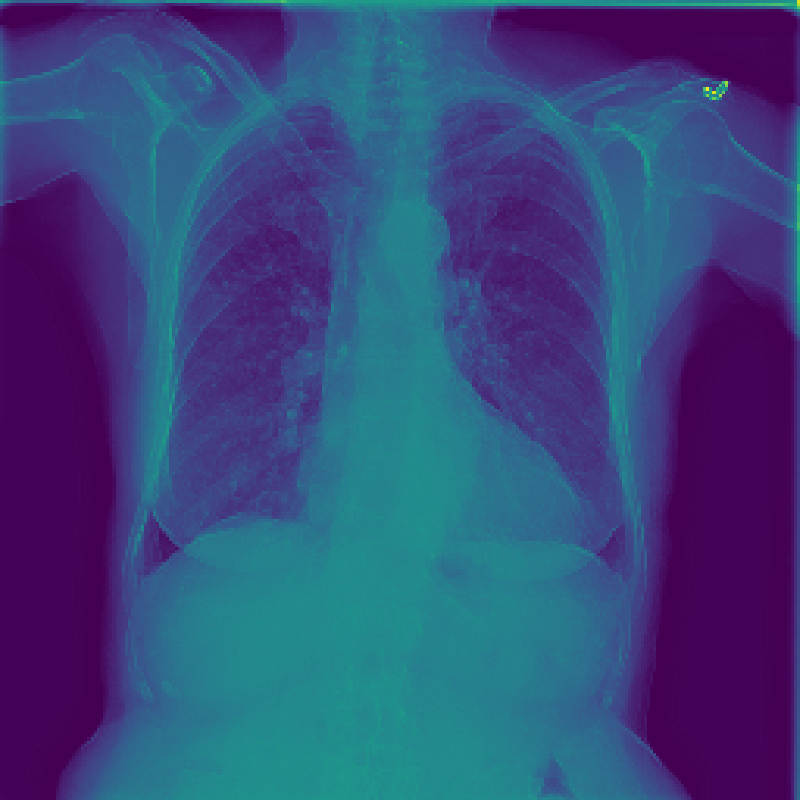

Figure 3: The feature map visualization of the GMSM and QCM modules. (a) Original image; (b) f1subscript𝑓1f_{1}italic_f start_POSTSUBSCRIPT 1 end_POSTSUBSCRIPT in Eq. 1; (c) f2subscript𝑓2f_{2}italic_f start_POSTSUBSCRIPT 2 end_POSTSUBSCRIPT in Eq. 1; (d) f3subscript𝑓3f_{3}italic_f start_POSTSUBSCRIPT 3 end_POSTSUBSCRIPT in Eq. 1; (e) Output of GMSM y𝑦yitalic_y; (f) Output of QCM; (g) Residual between y𝑦yitalic_y and QCM output.

3.2 Visualization of Feature Maps

In this section, we visualize the feature maps of the GMSM and QCM modules, as shown in Figure 3. From Figures 3 to 3, we observe that, during GMSM’s downsampling process, the earlier layers effectively capture the skeletal and organ contours in the X-ray image, while the later layers extract more abstract features. This observation suggests that GMSM progressively extracts key information in a coarse-to-fine manner. As shown in Figure 3, the output from the QCM module closely resembles the feature map of y𝑦yitalic_y in Figure 3. Additionally, the residual map in Figure 3 appears generally darker, indicating the QCM module’s effectiveness in compensating for quantization loss.